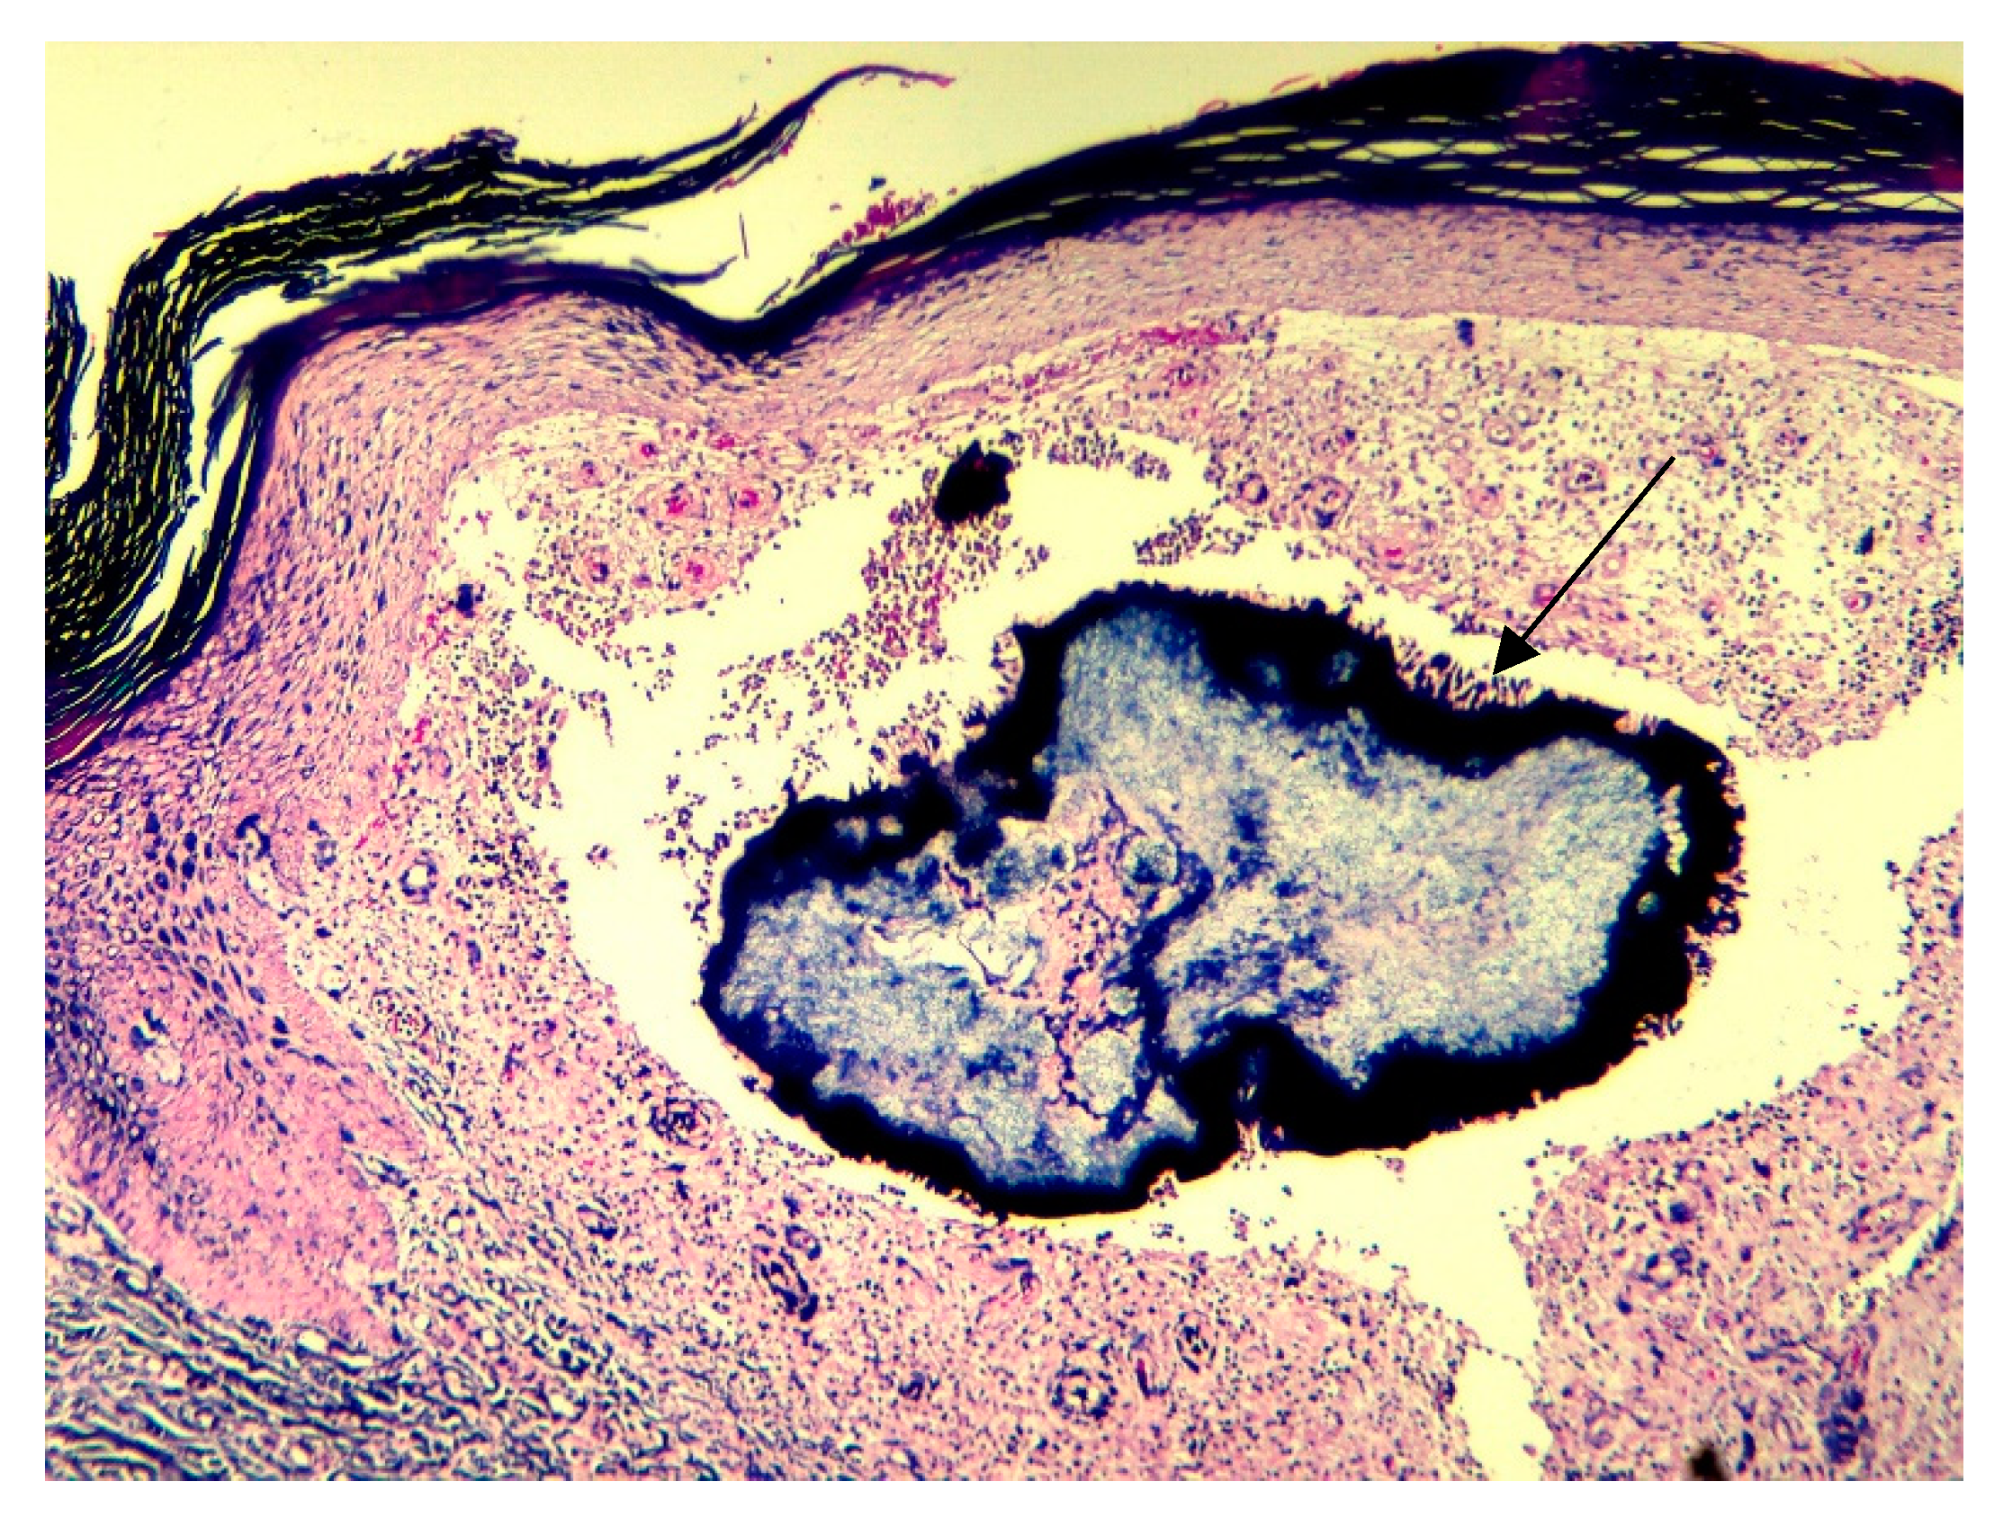

A skin biopsy was performed to exclude the possibility of malignancy, particularly Kaposi sarcoma. The biopsy revealed multiple colonies of filamentous organisms with characteristic neutrophilic outlining (Splendore-Hoeppli phenomenon), tumefied neoformed vessels, and an extensive mixed inflammatory reaction consistent with actinomycosis (Figure 4). The periodic acid-Schiff stain (PAS) was negative for fungal agents (Figure 5). The Gram stain showed conglomeration of filamentous Gram-positive bacilli (Figure 6). The culture of the specimen was negative, which is possible in cases of Actinomyces infection due to previous administration of antibiotics or inadequate culture conditions.

Figure 4. Histopathology findings suggestive for actinomycosis showing aggregates of bacteria surrounded by intensely eosinophilic material, Spendore–Hoeppli phenomenon reaction (arrow) and a densepolymorphous inflammatory infiltrate (10×, H&E stain).